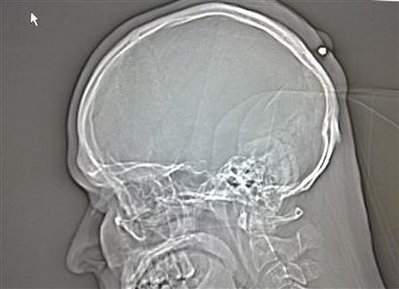

Check out this X-Ray of the bullet in his head!!

The discovery was made when he recently went to the doctor to have a lump examined. Police are not treating the incident as malicious: “It may have been a shot fired up in the air which entered his head on the way down.”